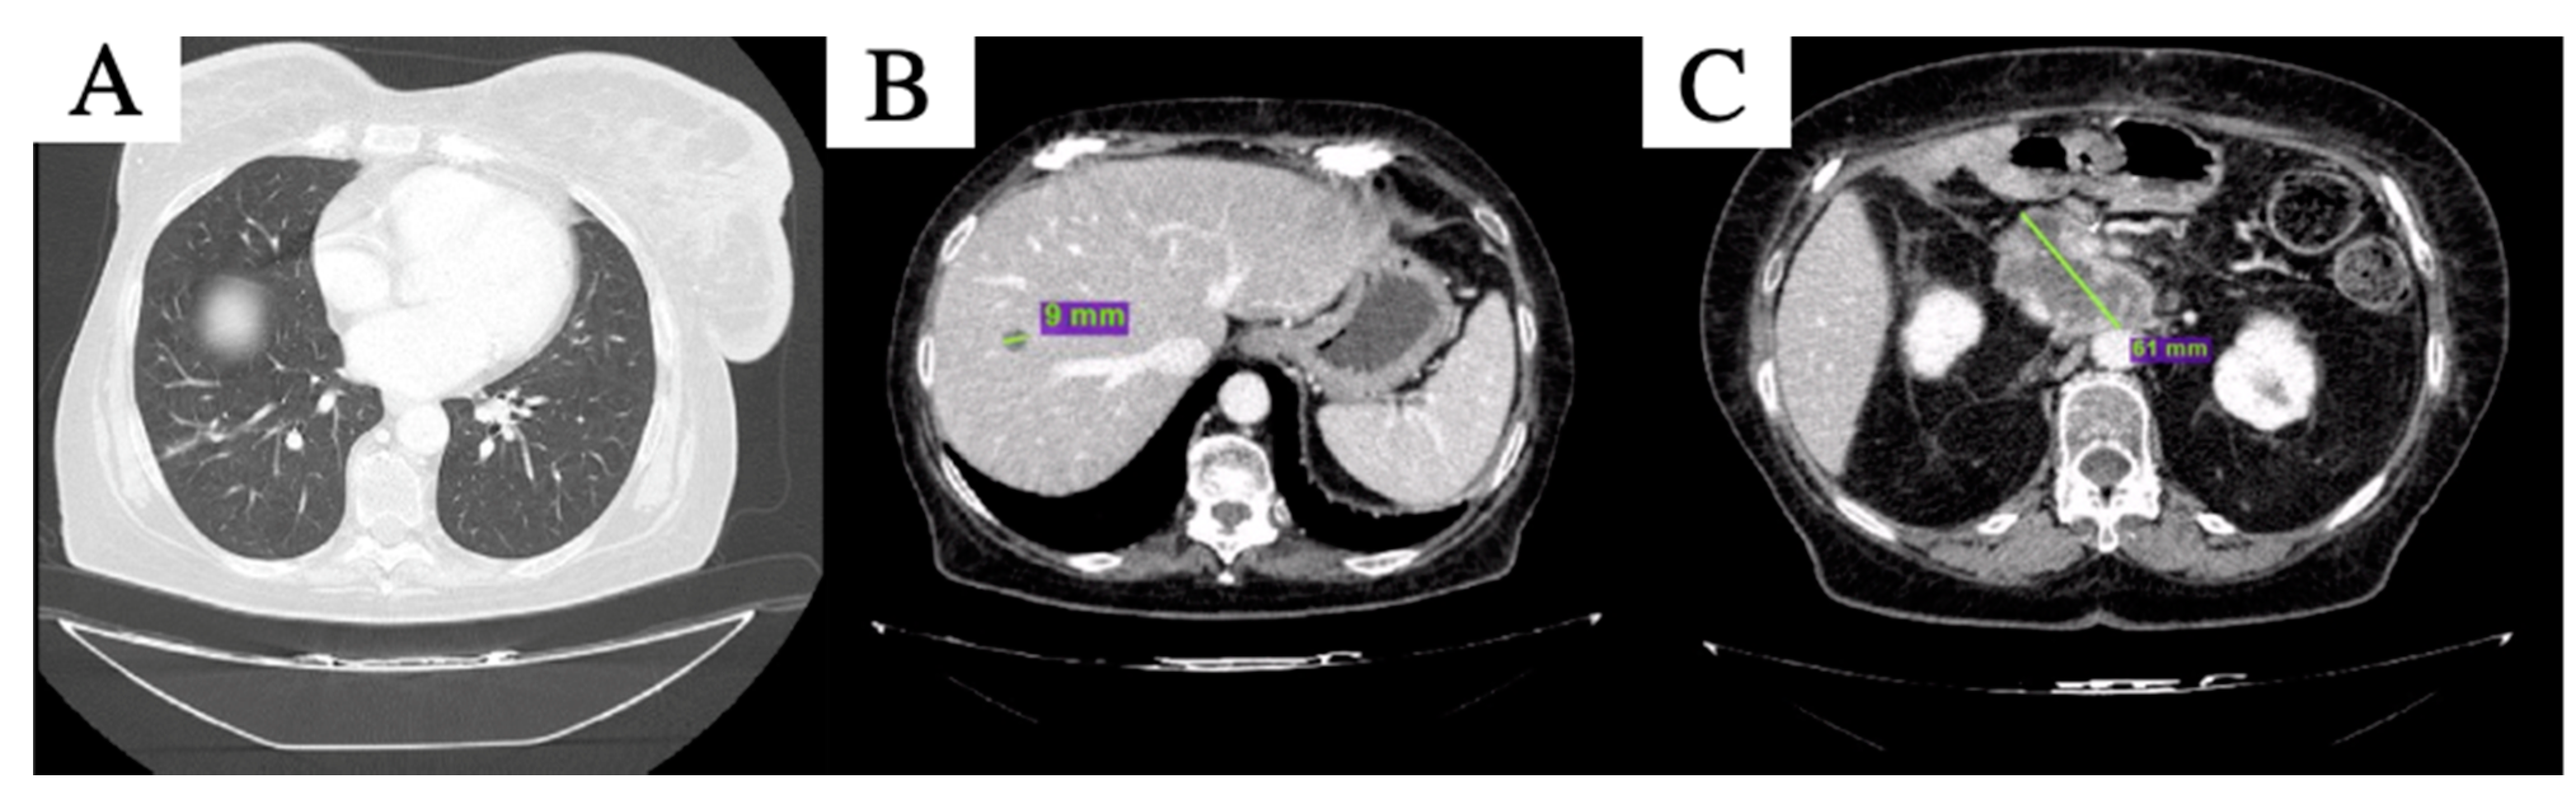

2. Case Description